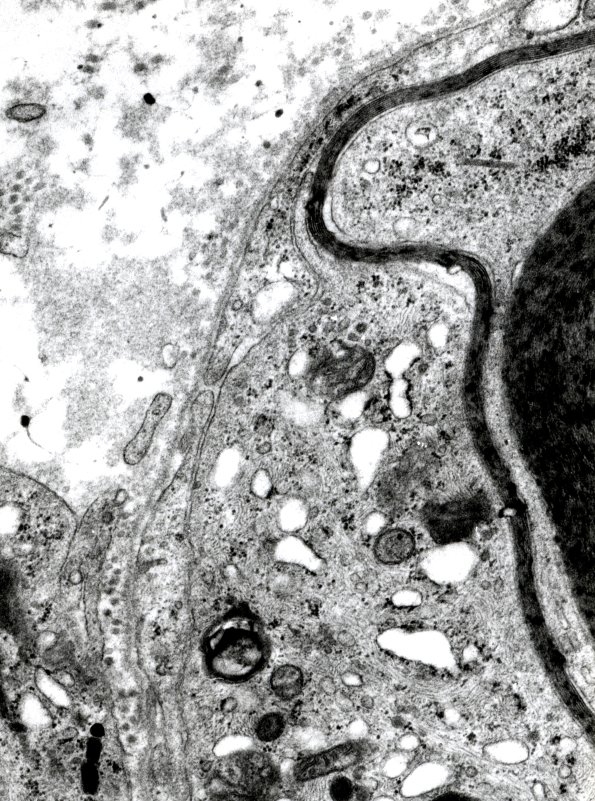

A superior portion of the macrophage stripping of the myelin sheath. (electron micrograph)